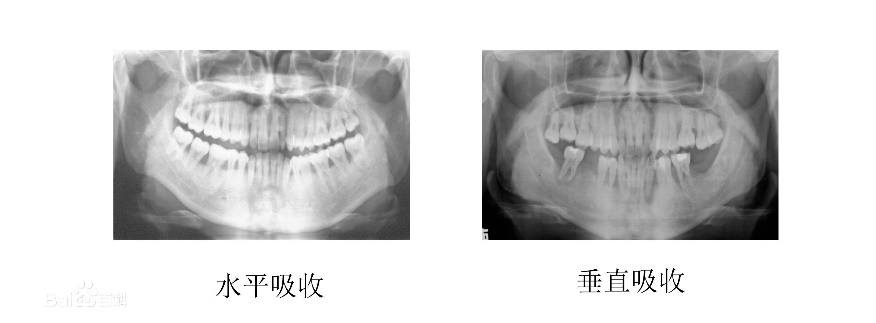

牙槽骨的吸收分为,水平吸收,垂直吸收和混合吸收三个类别。

- 水平吸收就是牙槽骨的整体高度发生下降,每一个牙根在牙槽骨中的部分都有减少。

- 垂直吸收就是牙槽骨发生斜向或者垂直方向的吸收,高度降低不多但是牙根部位会有比较明显的吸收现象。